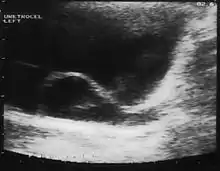

A ureterocele is a congenital abnormality found in the ureter. In this condition the distal ureter balloons at its opening into the bladder, forming a sac-like pouch. It is most often associated with a duplicated collection system, where two ureters drain their respective kidney instead of one. Simple ureterocele, where the condition involves only a single ureter, represents only twenty percent of cases.

Since the advent of the ultrasound, most ureteroceles are diagnosed prenatally. The pediatric and adult conditions are often found incidentally, i.e. through diagnostic imaging performed for unrelated reasons.

IVU-shows Adder head appearance or Cobra head appearance. Cystoscopy-shows translucent cyst which is thin walled surrounding ureteric orifice